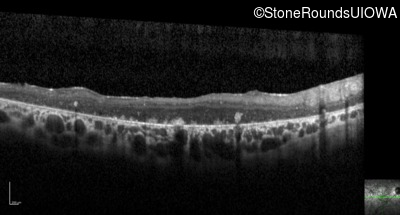

Optical Coherence Tomography - Left - 20/400 sc

Exemplar / OCT Stack